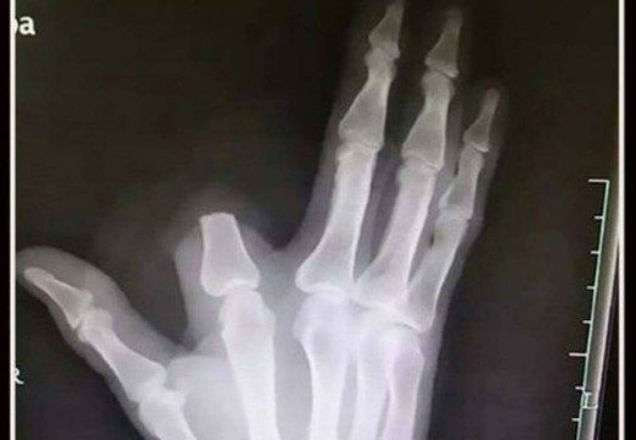

Radiografia mostra como ficou a mão do paciente (Foto: Reprodução)

Na verdade, a picada da cobra causa apenas sangramento, dor e inchaço na região. Para piorar a situação, o agricultor deixou o dedo cortado no local. Caso tivesse levado o membro para o hospital, os cirurgiões poderiam reimplatá-lo com sucesso.